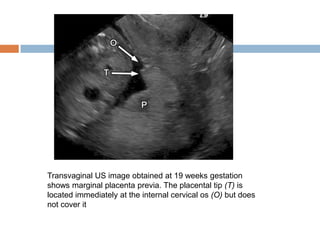

Transvaginal US image obtained at 19 weeks gestation

shows marginal placenta previa. The placental tip (T) is

located immediately at the internal cervical os (O) but does

not cover it

Transvaginal US imageobtained at 19 weeks gestation shows marginal placenta previa. The placental tip (T) is located immediately at the internal cervical os (O) but does not cover it